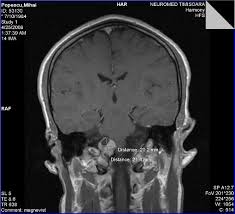

Dr Frantescu Neurochirurg Timisoara